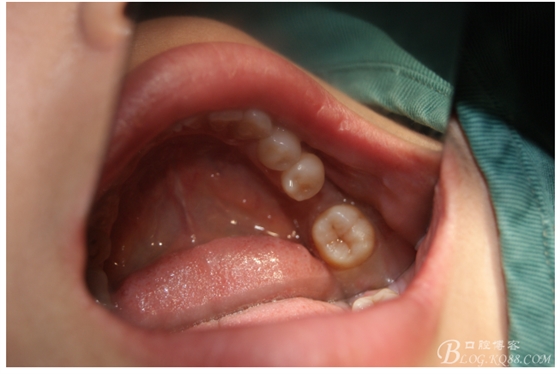

檢查:36.46缺失,36缺牙區(qū)近遠(yuǎn)中間隙約3mm,46缺牙區(qū)間隙約0.5mm,37.47.48近中傾斜,48近中面齲壞達(dá)牙本質(zhì)淺層,37牙周探診4mm,47近中探診深度5-6mm,不松,口內(nèi)照片及CT片如下:

口內(nèi)照片